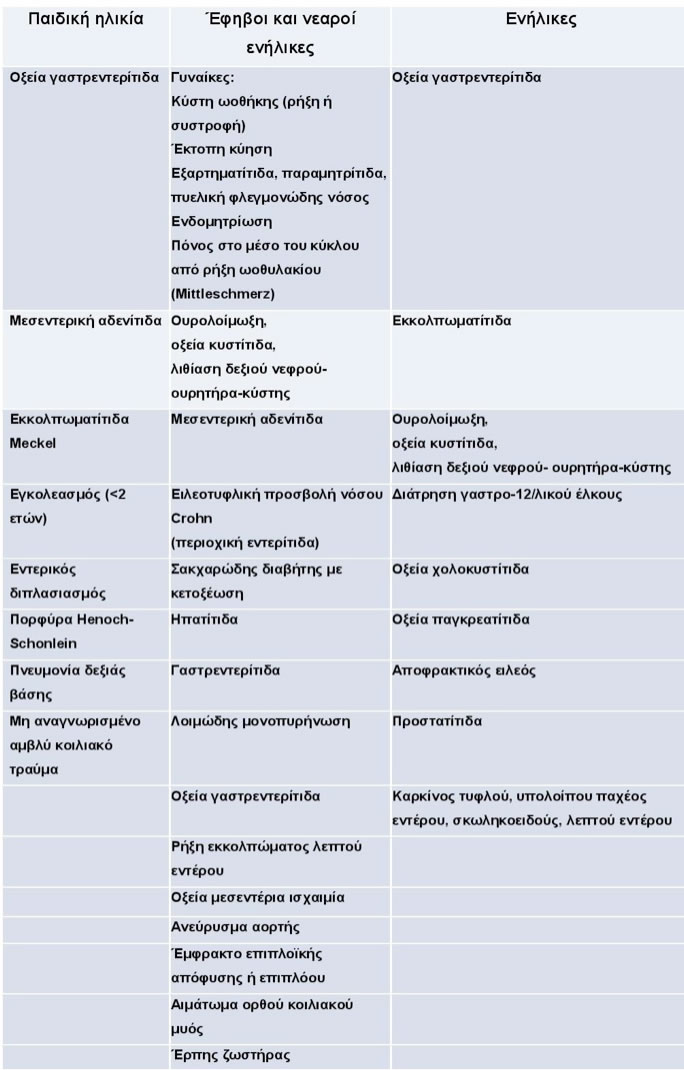

Διαφορική διάγνωση

Μία πλειάδα παθήσεων που εμφανίζονται με εικόνα οξείας κοιλίας περιλαμβάνονται στη διαφορική διάγνωση της οξείας σκωληκοειδίτιδας (Πίνακας 5).

Πίνακας 5.

Διαφορική διάγνωση της οξείας σκωληκοειδίτιδας ανάλογα με την ηλικία